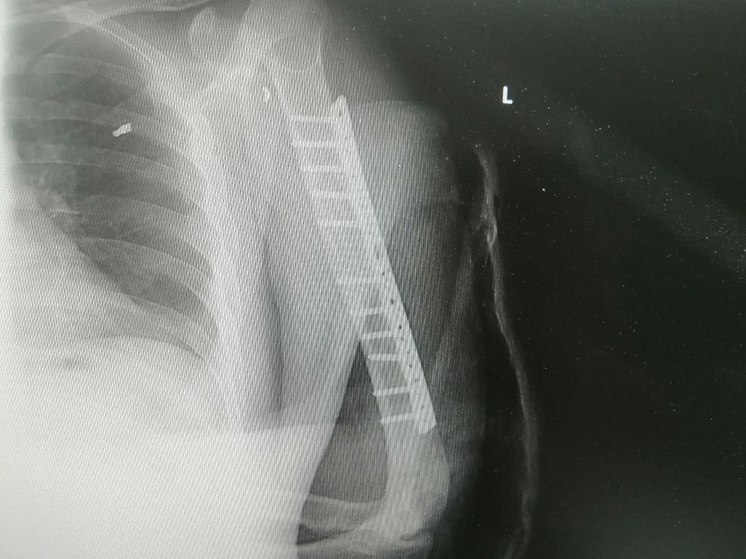

Фото Сургутской травматологии

39-летний мужчина с минно-взрывной травмой вскоре сможет спокойно двигать рукой. Благодаря слаженной работе бригады врачей Сургутской травматологии мужчина получил такую возможность. Об этом сообщается в telegram-канале медучреждения.

Обследование пациента выявило повреждение лучевого нерва. Чтобы исправить ситуацию, нужно было пересадить аутотрансплантат. Для этого в микрохирургической операции понадобились несколько врачей.

Травматологи-ортопеды Владимир Кельметр и Алексей Котов оперировали пациента более четырех часов. В ближайшие две недели пациента будут наблюдать.